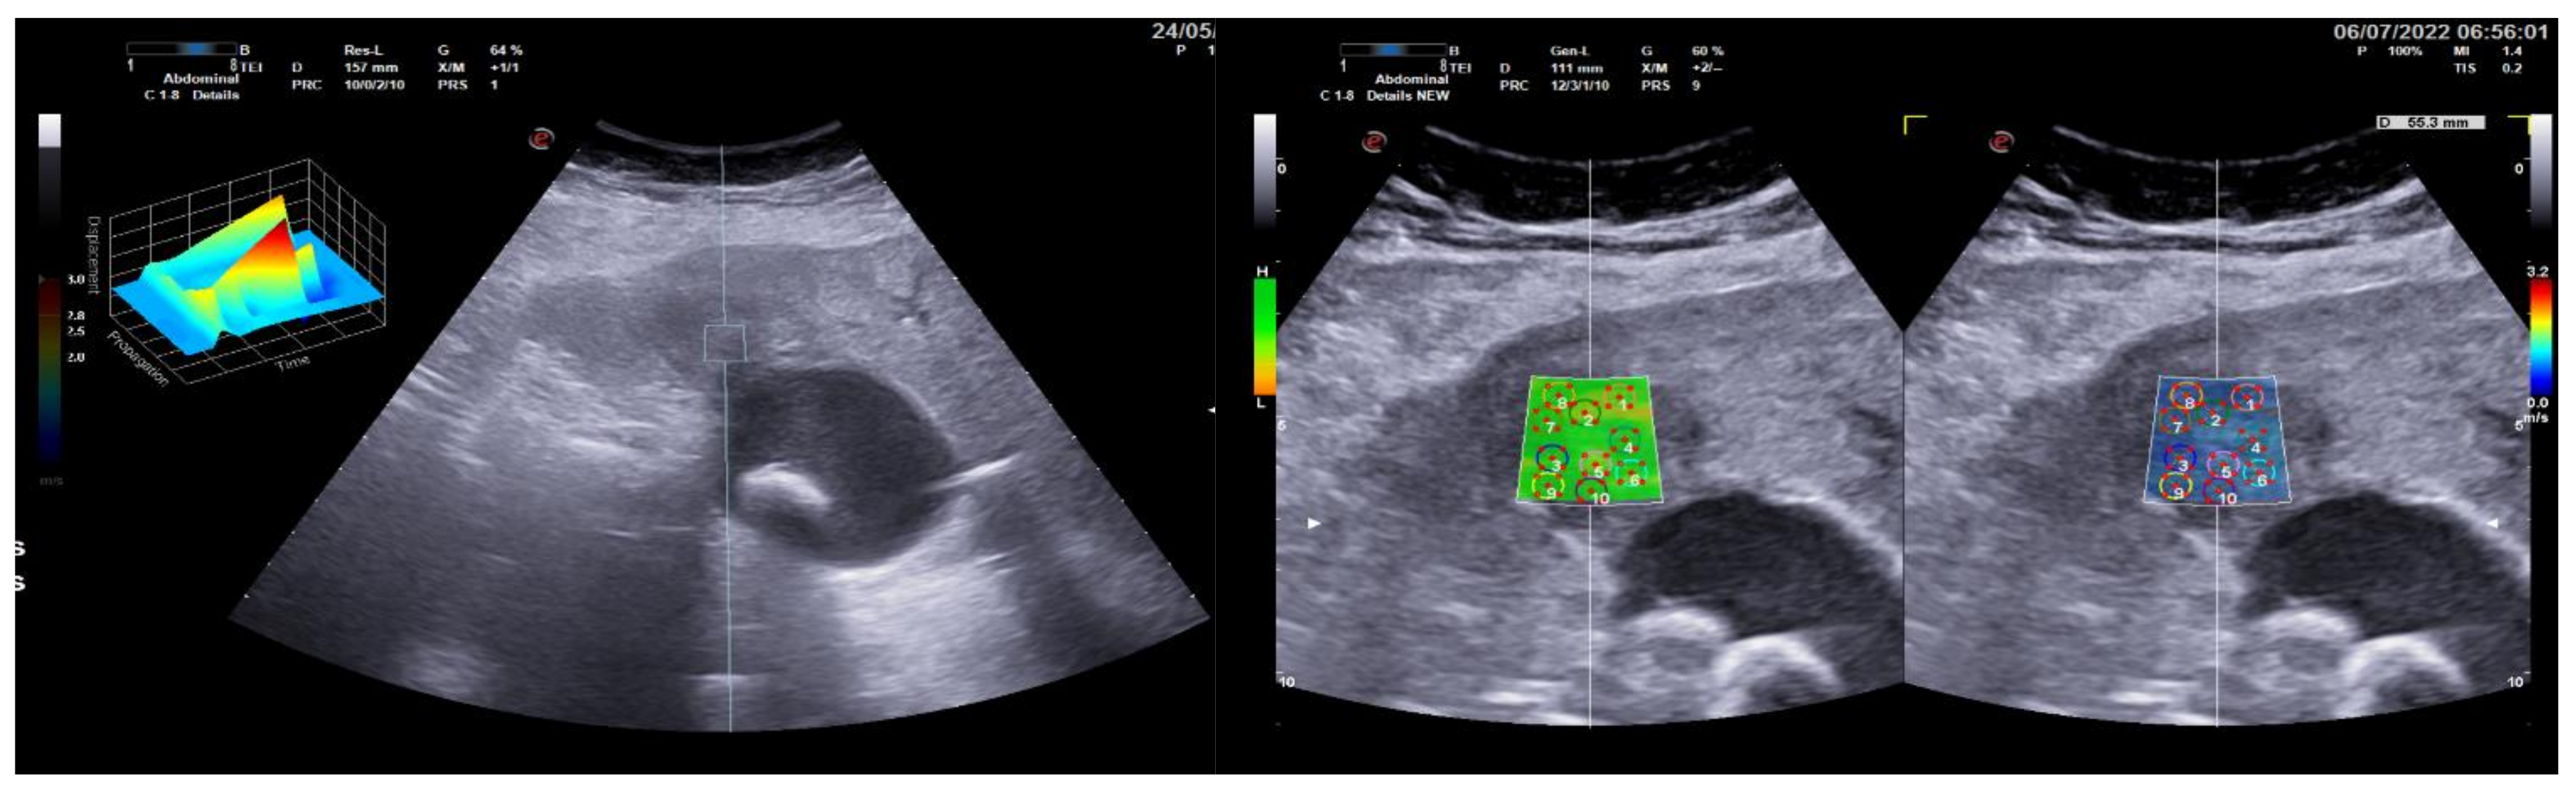

3.1. Group 1: Benign Focal Liver Lesions (Hemangiomas)